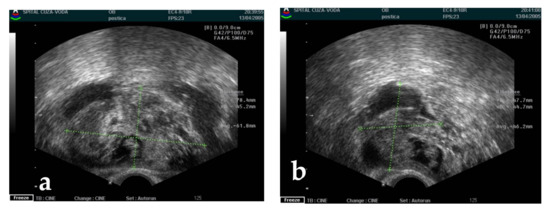

4.1. Diagnosis Approach